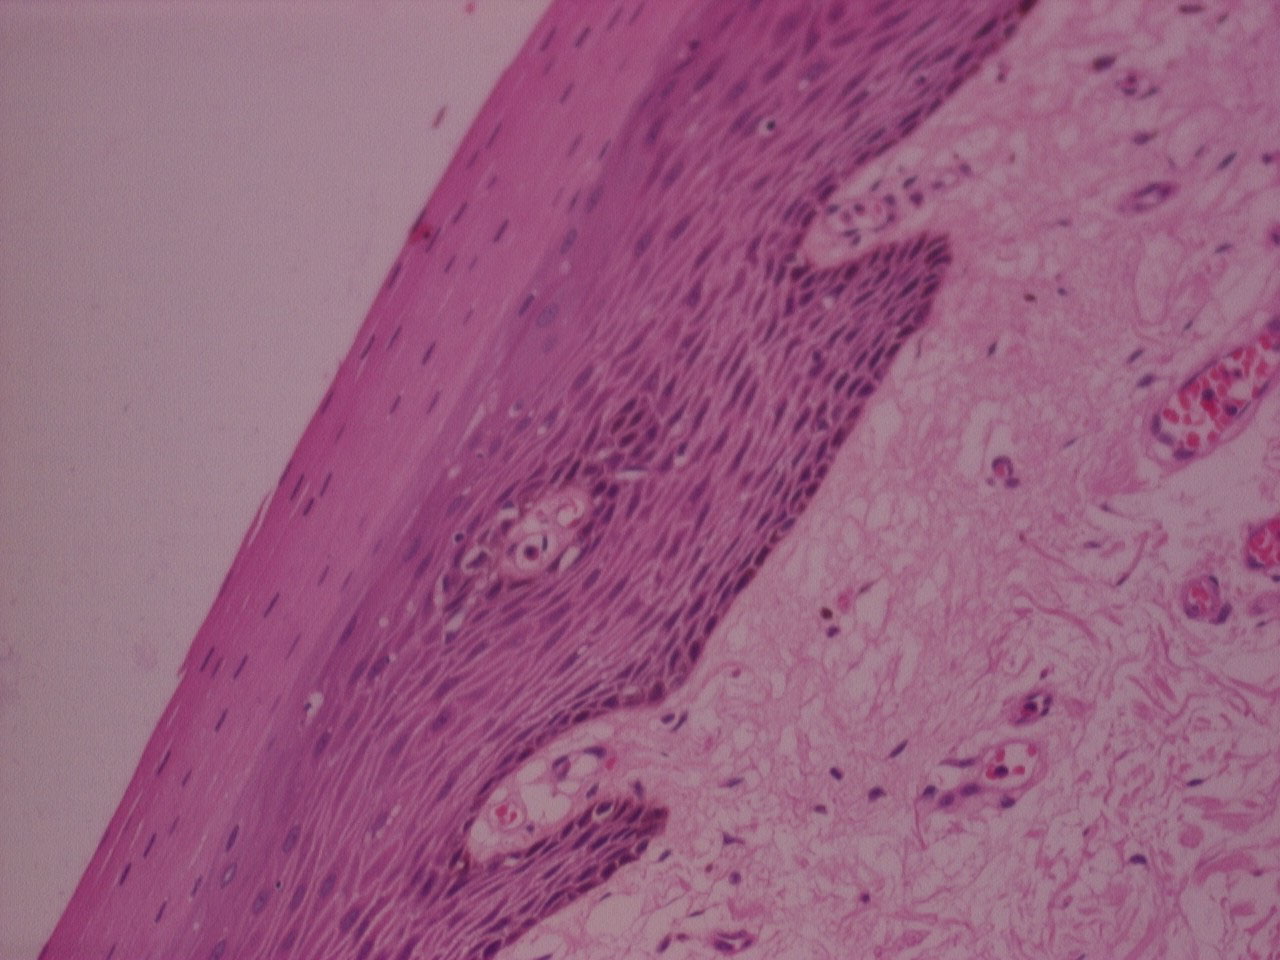

Mann-Whitney U Test displayed p value (> 0.05) , that was statistically not significant, for all criteria's indicating comparable clarity, uniformity, cell morphology, section quality, crispness, nuclear cytoplasmic contrast, nuclear staining, cytoplasmic staining and IHC staining between n-Heptane and xylene (Figure 1, Figure 2, Figure 3, and Figure 4).

Figure 1: H&E stained photomicrograph of section processed with n-Heptane, 10x. View Figure 1